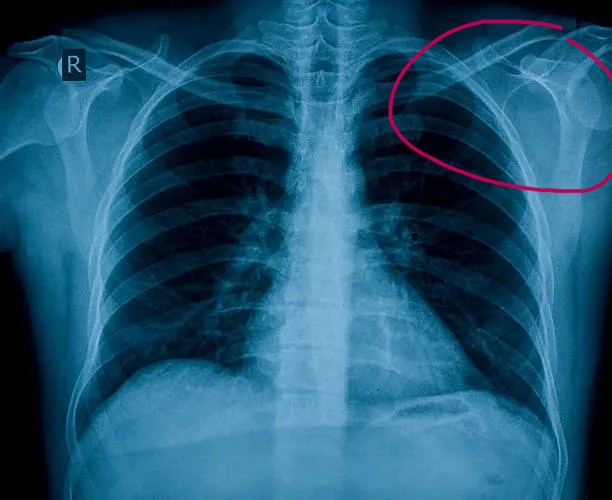

if i had to highlight an area it's here. both my shoulders came out before but this might not be related.. im not sure. i'm healthy 22yo no drugs, smoking. what doctor should i go to?